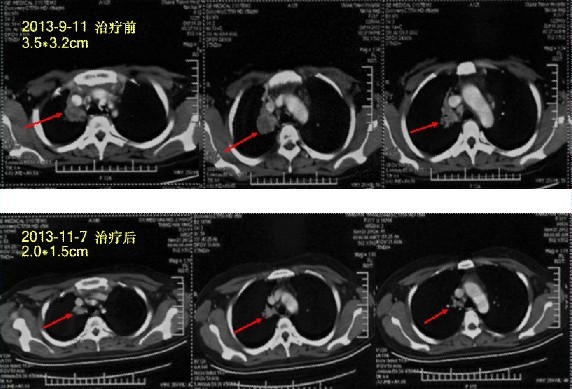

患者姓名:马小姐,33岁,确诊为肺癌

简要病史:经过朋友推荐来到广州中医药大学金沙洲医院肿瘤综合诊疗中心医院进行检查,检查后诊断右肺上叶肺癌,纵膈淋巴结转移,腰椎转移,心包积液,多发骨转移,多发脑转移,手术风险很大,朋友、家人都着急了,患者自己也慌了,听从专家的安排,进行多学科综合治疗治疗:WB-1无创全身热疗系统+基因治疗,两个疗程之后,患者健康恢复显著,半个月患者出院。